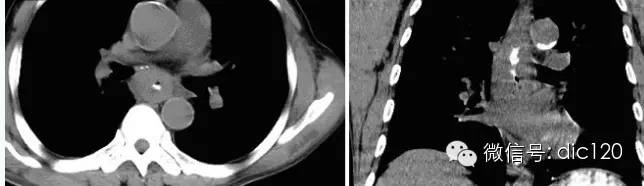

【病史臨床】男,63歲,胸痛,進行性吞咽困難伴消瘦20天。

【影像圖片】【影像表現(xiàn)】 CT:表現(xiàn)現(xiàn)為食管壁明顯增厚,管腔狹窄;食管與周圍結(jié)構(gòu)分界不清食管吞鋇:食管中段充盈缺損,管腔不規(guī)則狹窄,管壁僵硬,粘膜糾集破壞,與正常食管壁分界清晰。

【診斷】 病理診斷:食管(中下段)高-中分化鱗狀細胞癌,侵及食管壁全層。(圖1.2)